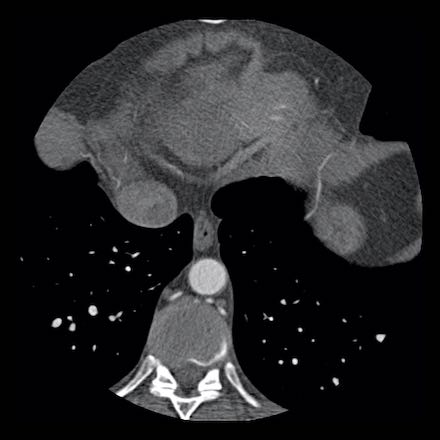

Continue with the next images of the same patient…

Same patient.

Double-oblique (A) and volume-rendered (B) images of the LAD showing the

location and the length of the plaque.

Also, the stenosis in the D2 branch of the LAD can be appreciated on the volume

rendered reconstruction.

Due to the degree of stenosis and the presence of napkin-ring sign (visible on

axial images) this patient underwent ICA where the presence of severe stenosis

was confirmed.